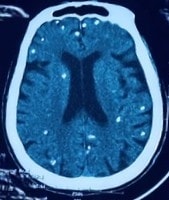

Nang sán dây lợn 'phát sáng' khắp cơ thể người phụ nữ

Người phụ nữ 77 tuổi rối loạn ý thức, ảnh chụp CT sọ não và X-quang ngực cho thấy nang sán dây lợn vôi hóa chi chít trong não và cơ thể.